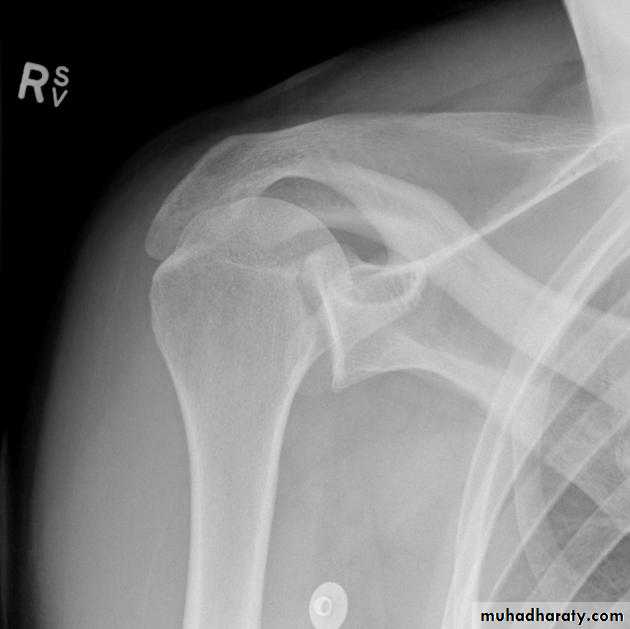

One of the large joints that commonly dislocated.-Anterior shoulder dislocation:

*most common type about 96% of total shoulder dislocation.

*40% recurrent.

* 15% fracture greater tuberosity.